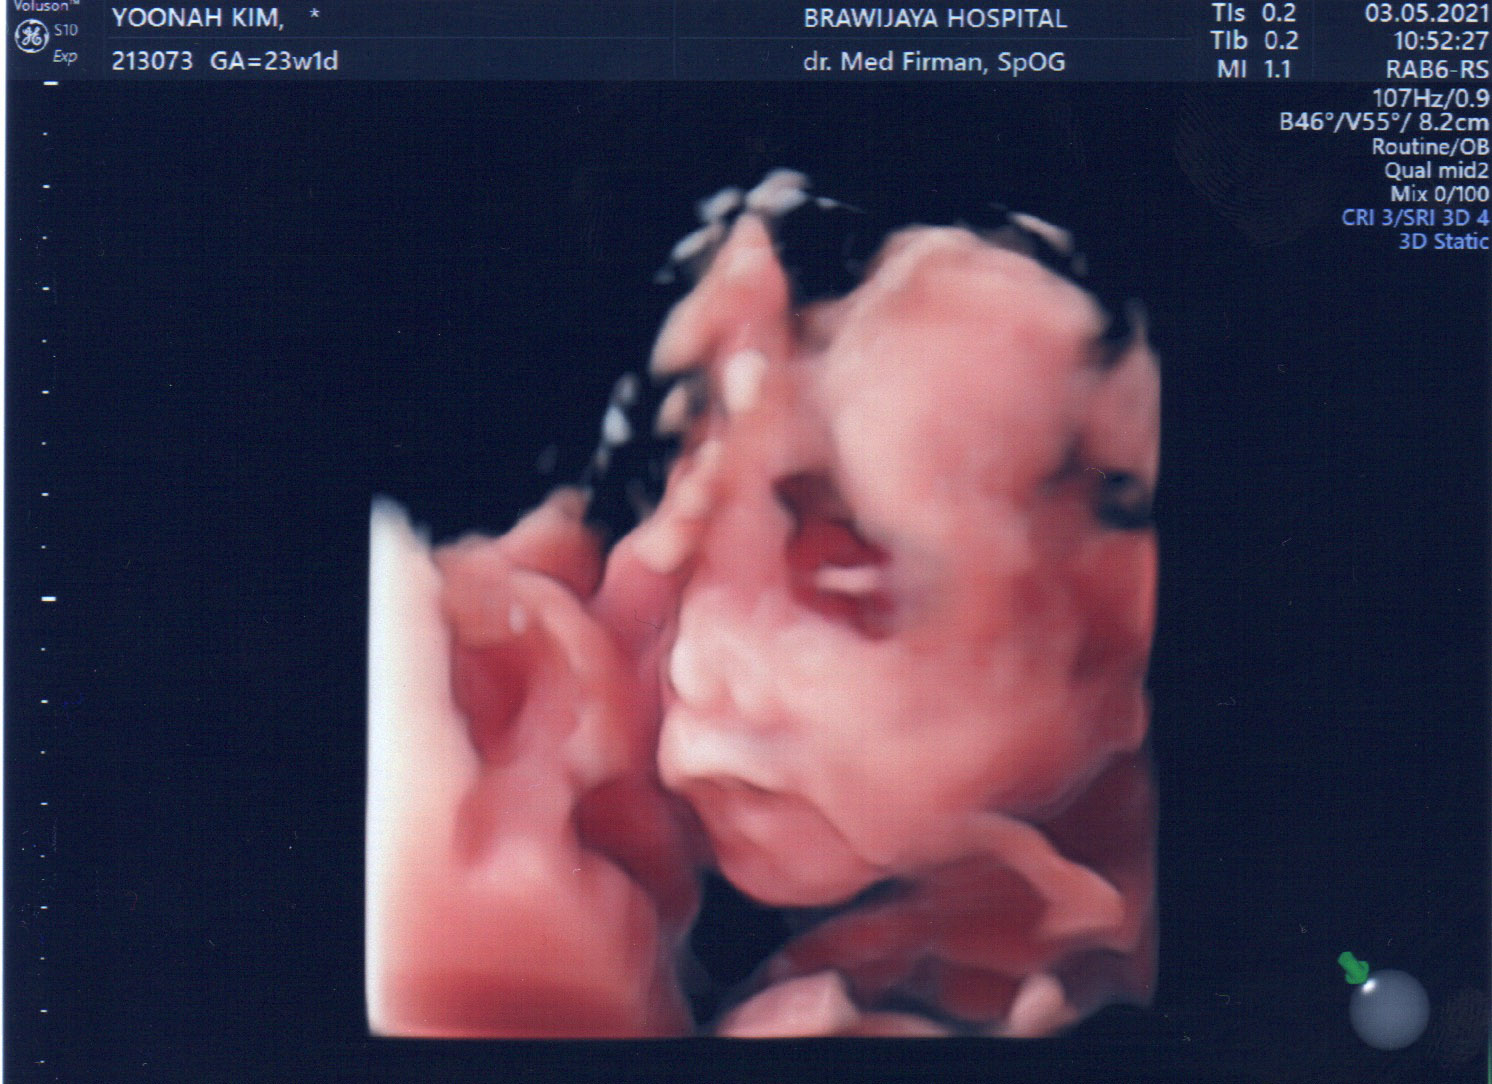

23주만에 드디어 얼굴을 보여주신 울 아드님...

집사람은 코가 낮은 거 같다고 걱정한다. ㅎㅎㅎ

설사 코가 낮다고 하더라도 코가 자랄 시간은 아직 많이 남았다구~~!!